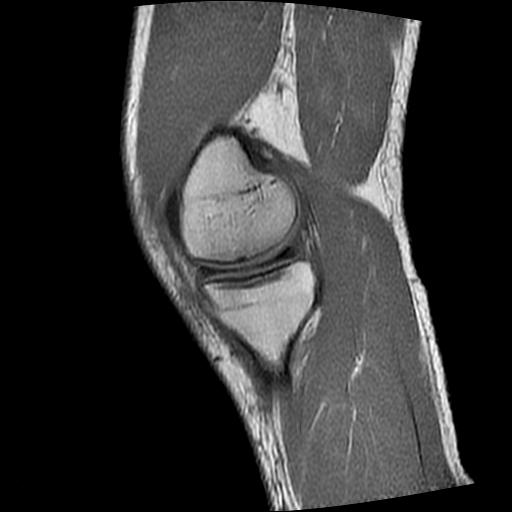

标题: MRI1265:男性40岁,右膝关节 [打印本页]

标题: MRI1265:男性40岁,右膝关节

40岁男性,右膝关节外伤,x光平片示,髁间隆突撕脱骨折。

1、前交叉韧带撕裂;

2、外侧半月板后角撕裂;

3、关节腔积液。

前交叉韧带撕裂,关节腔积液.

半月板1-2级损伤   前交叉韧带撕裂伤   关节腔少量积液  诸骨未见新鲜外伤性改变

髁间隆突撕脱骨折;内侧副韧带损伤。

内侧副韧带撕裂及关节腔积液是肯定的,但是前交叉撕裂确定吗?会不会有容积效应的因素,因为前一张前交叉显示清楚,连续性良好,且较光滑。请问楼主有关节镜支持吗?我们医院也经常有这样的患者,但苦于没有关节镜,而无法对照、证实(除非完全断裂),出现了不同的诊断结果只能毫无意义的争论。

1、前交叉韧、内侧副韧带撕裂;

3、关节腔积液。4、髁间脊撕脱骨折。

除了关节积液外并无韧带撕裂,acl胫侧附着点有2束,正常情况下脂肪信号。此病例应加做压脂像以便观察是否有骨损伤。